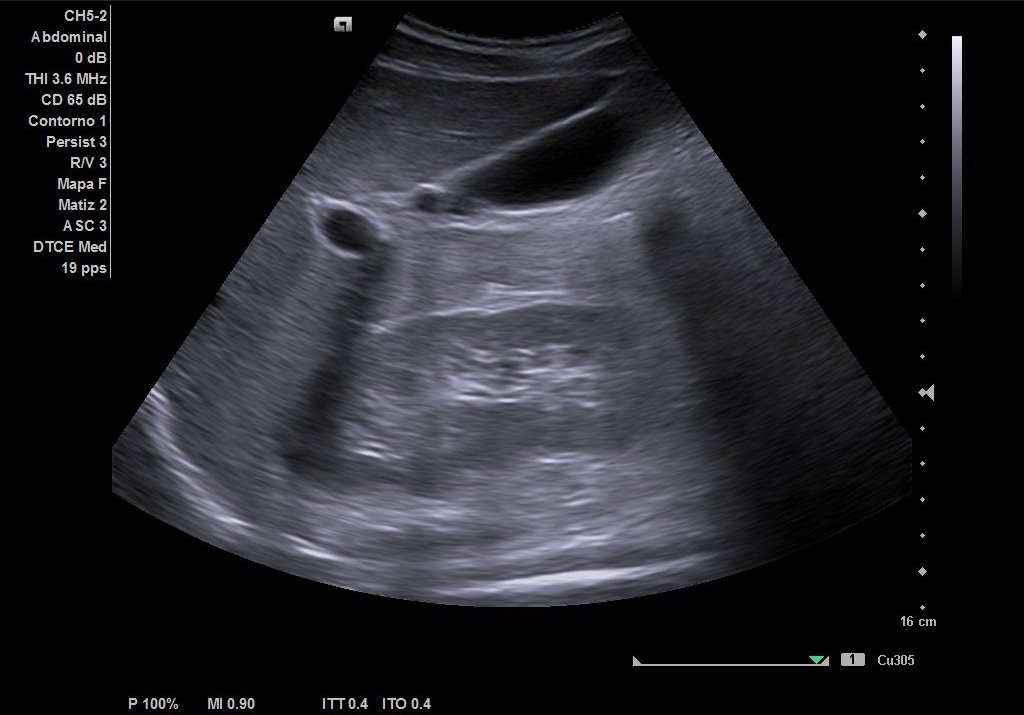

Hallazgos ecográficos

Como hallazgos, observamos dilatación del uréter proximal con hidronefrosis grado II-III. Sin visualización de imágenes compatible con litiasis. Riñón derecho de tamaño y ecoestructura normal sin dilatación de vía excretora. Vejiga vacía y ausencia de liquido libre.

Se deriva a Urgencias Hospitalarias para valoración y tratamiento. Se le realiza analítica sanguínea y de orina sin elevación de reactantes de fase aguda. Se solicita ecografía abdominal reglada, con hallazgos de litiasis en tercio medio de uréter izquierdo que condiciona hidronefrosis retrógrada grado III por lo que se contacta con Urólogo de guardia que cita en consultas externas para valoración.